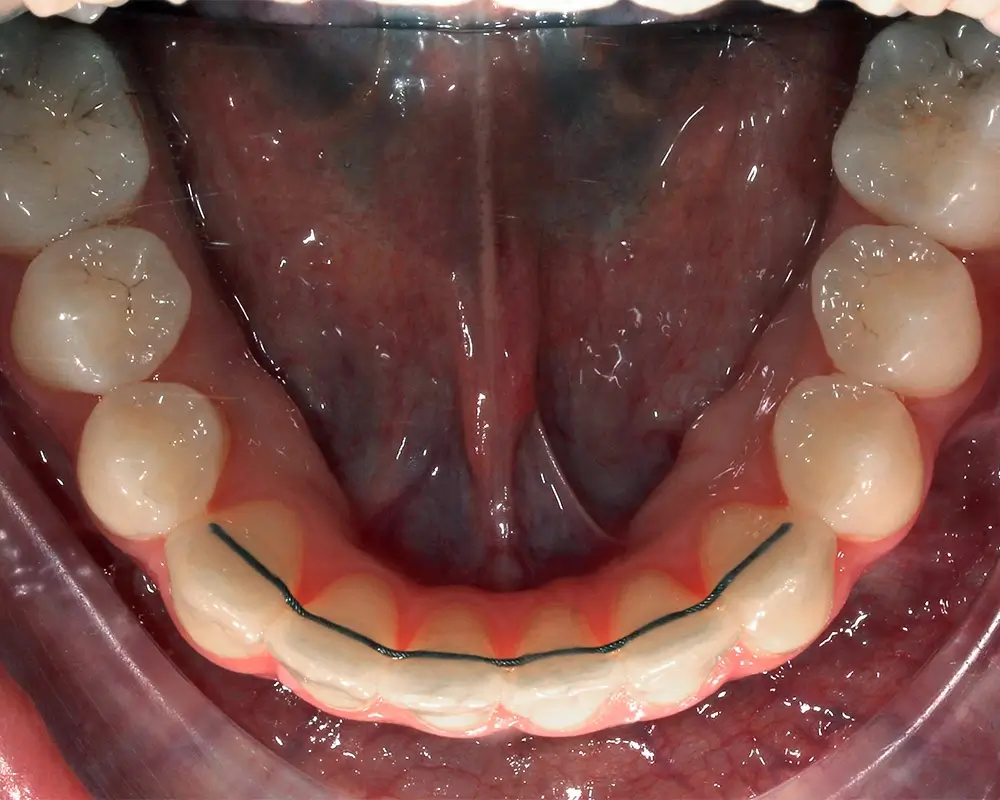

Эффективность устранения дефекта прикуса посредством элайнеров FlexiLigner.

Результаты лечения

ПОСЛЕ